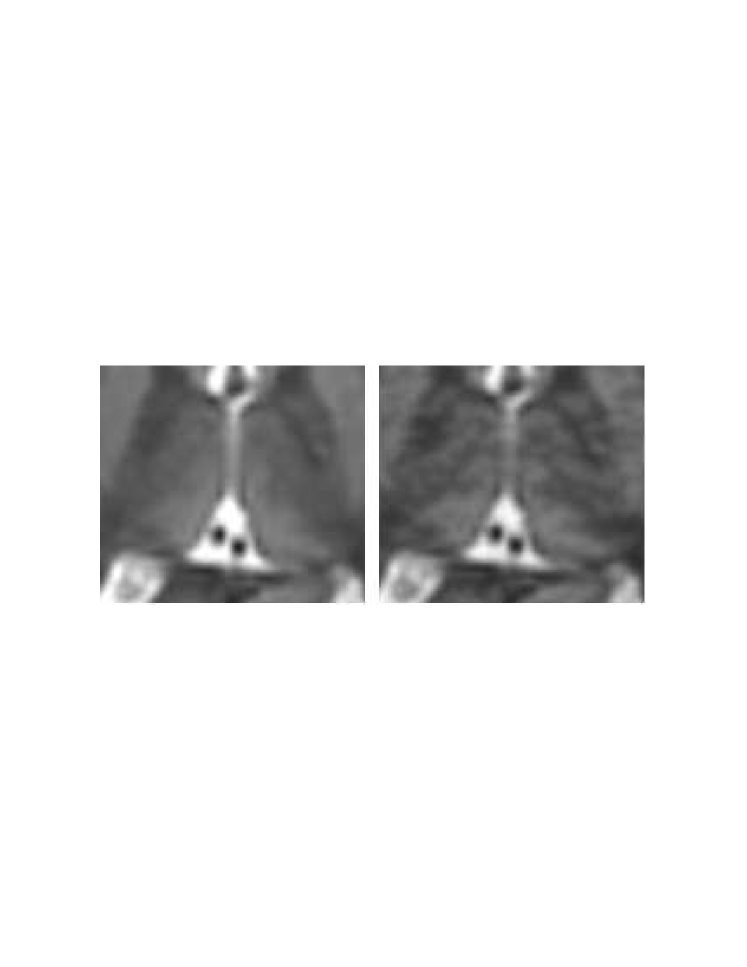

In this thesis, a novel coherent integrated methodology is introduced (theory, algorithm and applications) to reduce the dimensionality of high-dimensional datasets. The method constructs a diffusion process among the data coordinates via a random walk. The dimensionality reduction is obtained based on the eigen-decomposition of the Markov matrix that is associated with the random walk. The proposed method is utilized for: (a) segmentation and detection of anomalies in hyper-spectral images; (b) segmentation of multi-contrast MRI images; and (c) segmentation of video sequences.

This thesis is composed of three parts. In the first part, we introduce the novel Diffusion Bases methodology (theory, algorithms and applications) for dimensionality reduction. Specifically, in Chapter 2 we give an in depth introduction to dimensionality reduction where we provide a formal definition of the problem followed by a description of the current state-of-the-art techniques for dimensionality reduction. In Chapter 3 we describe in details the diffusion maps technique [45] since it is closely connected to our diffusion Bases (DB) dimensionality reduction scheme which we introduce in Chapter 4. The DB algorithm explores the variability among the coordinates of the original data while the DM explores local neighborhoods of points in the dataset. Both algorithms use a random walk model. The DB algorithm uses the eigenvectors of the corresponding Markov matrix as an orthonormal system and projects the original data onto it to obtain the low-dimensional representation. The DM algorithm, on the other hand, builds a different Markov matrix whose eigenvectors constitute the low-dimensional representation. In Chapter 5 we provide an introduction to hyper-spectral imagery which includes the terminology, concept, motivation and common applications in this area. Chapter 5 is necessary for the understanding of Chapters 6 and 9. Chapters 6-8 include successful applications of the DB scheme. Specifically, in Chapter 6, the DB dimensionality reduction scheme is used for segmentation of hyper-spectral images and for the detection of anomalies in images of this type. In Chapter 7, the DB scheme is incorporated in an algorithm for segmentation of multi-contrast MRI images. Segmentation of video sequences which uses the DB scheme is described in Chapter 8.